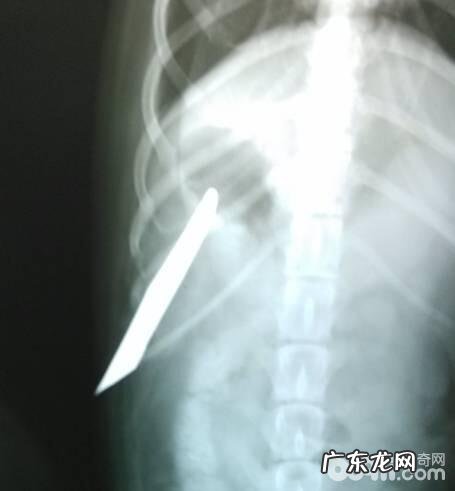

X光侧方片观查 , 刀刺进的深层

X光腹背位探察刀刺进的深层和总宽